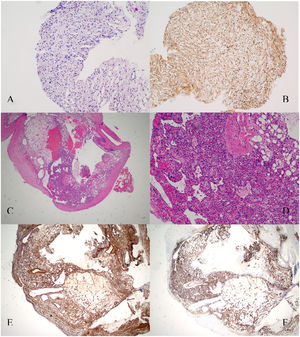

To confirm the cause of the mediastinal lesion, the patient underwent medical thoracoscopy. A hypervascular, sessile mass was observed in the prevascular mediastinum and subsequently biopsied (Fig. 2). The tumour was not separated from the aorta during the procedure. Histological examination of pleural fragments showed vascular congestion, alveoli filled with macrophages, and compression of the alveoli by a fibroadipose tissue 'mass' (MDM2-) and smooth muscle (actin+), accompanied by capillary proliferation (CD34+). Thrombi were frequently present. No necrosis or mitoses were detected. Histochemical investigation for microorganisms, including PAS, Ziehl-Neelsen, and Grocott staining, yielded negative results. Immunohistochemical analysis was performed to explore other neoplasms, and results for calretinin, BER-EP4, S100, CD1a, Melan-A, HMB45, and p53 were negative (Fig. 3)

Histopathology sections. A. Lesion in the pectoralis major muscle sheath. Hematoxylin and eosin staining. B. Lesion in the pectoralis major muscle sheath. Schwann cells are strongly positive for S-100 protein (×10). C. Hematoxylin and eosin staining revealing features of the excised pleural mass with mature adipose tissue, thick-walled blood vessels and smooth muscle cells. Pathological findings of angiomyolipoma. D. 10× magnification. E. Pleural lesion. Smooth muscle actin immunohistochemical showed diffuse positivity smooth muscle cells (×10). F. Pleural lesion. Immunostaining for CD34 antigen revealed many CD34-reactive capillaries combined with mature adipocytes (×10).

Angiomyolipomas are characterised by the expression of melanoma markers (HMB45 and melan-A) in tumour cells, as well as smooth muscle component positivity for muscle actin-specific marker (HHF35) and desmin.2,8 Although the immunohistochemical study did not fully support the diagnosis, the observed morphological features strongly suggest that angiomyolipoma is likely the correct diagnosis, considering its rarity in the mediastinum and the limited number of reported cases in the literature. The histology was reviewed by three different pathologists.